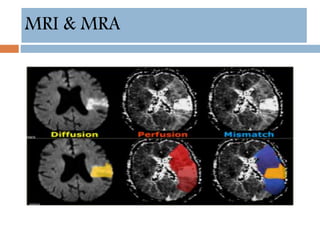

MRI & MRA